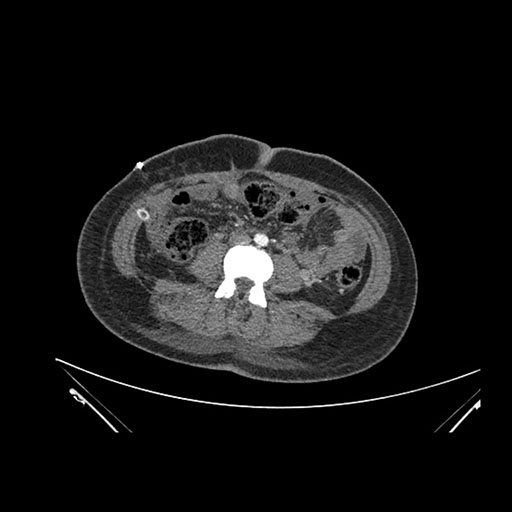

Axial Venous

Coronal Venous

Imaging analysis

Based on initial findings, which issue(s) would you be most concerned about?